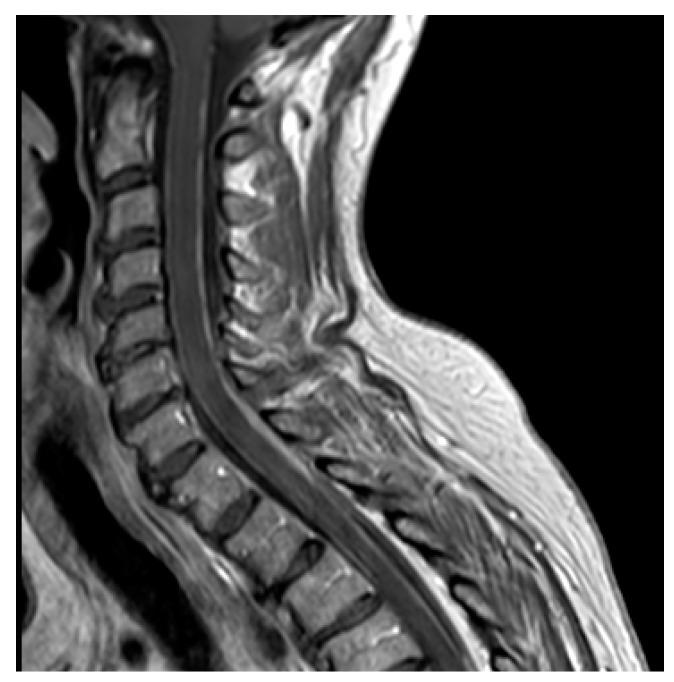

实体瘤的软脑膜转移(LM)由于早期使用MRI进行诊断以及靶向药物和免疫治疗后某些分子亚组的预后改善,已成为日益重要的未满足需求。在本综述中,我们首先讨论了限制靶向药物在LM中疗效的因素,例如原发性肿瘤与中枢神经系统病变之间的分子差异以及正常脑、脑肿瘤和脑脊液水平的中枢神经系统屏障。此外,我们回顾了发病机制、实验模型和方法,如MRI(采用RANO和ESO/ESMO标准)、脑脊液细胞学检查和液体活检,以改善治疗后的诊断和监测。报告了针对EGFR突变和ALK重排的非小细胞肺癌、HER2阳性乳腺癌和BRAF突变黑色素瘤的LM的靶向治疗的疗效和局限性,包括鞘内给药或传统细胞毒性化合物的改良使用。讨论了检查点抑制剂在不可靶向治疗的肿瘤,特别是三阴性乳腺癌的LM中的疗效。最后,我们重点介绍了一些改善药物递送的最新技术。